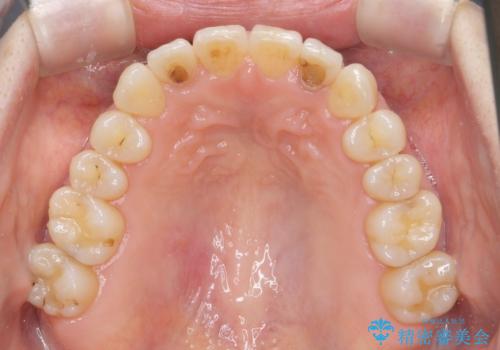

前歯の目立つガタつきをマウスピース矯正で治療

- 大きく傾いてしまった前歯のガタつきの改善を求めて来院されました。

前歯のガタつきをしっかりと取り、機能的・審美的に理想的な歯並びをマウスピース矯正で達成します。

強度のガタつきはマウスピース単体では並び切ることが難しいこともありますが、しっかりと装着していただいたことで良好な治療結果を得ることができました。